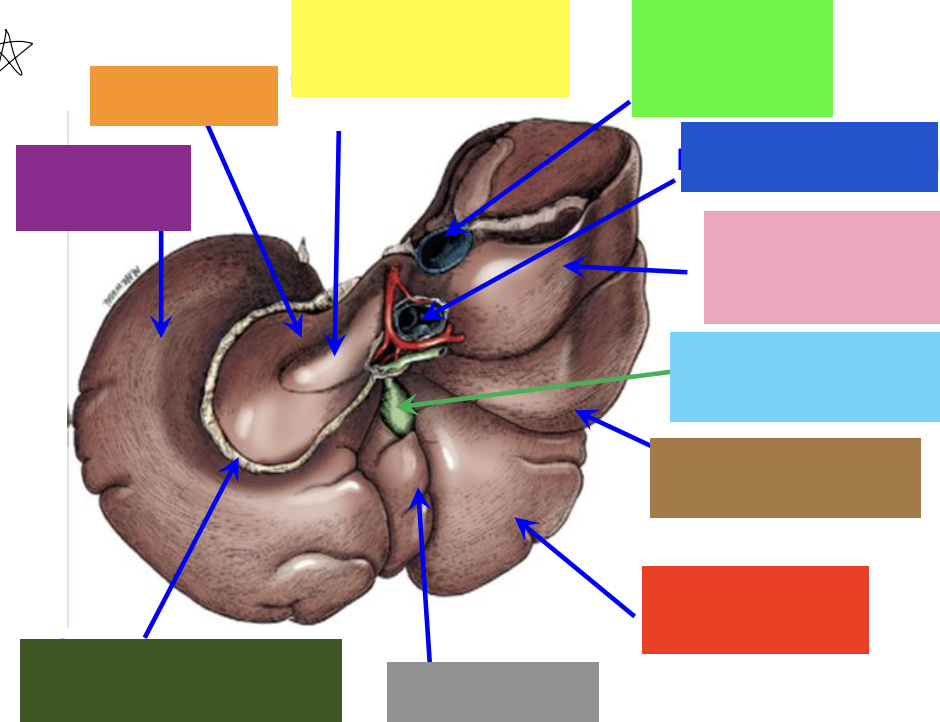

purple box

left lateral lobe

orange box

caudate lobe

yellow box

papillary process of the caudate lobe

neon green box

right lateral lobe

dark blue box

hepatic portal vein

pink box

caudate process of the caudate lobe

light blue box

gall bladder

brown box

right lateral lobe

red box

right medial lobe

grey box

quadrate lobe

dark green box

lesser omentum